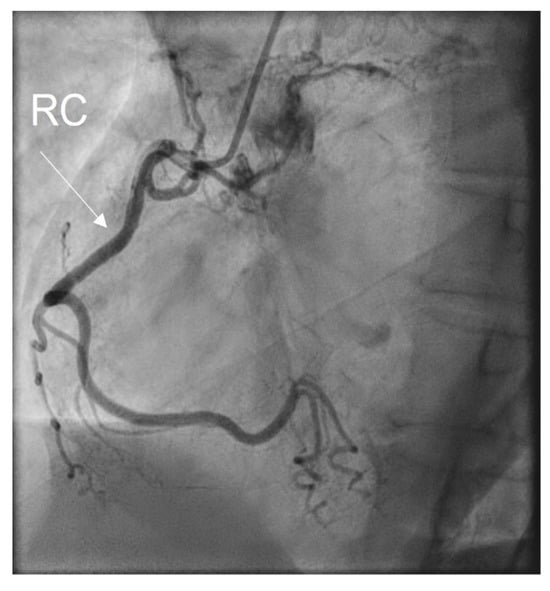

2. Case Presentation